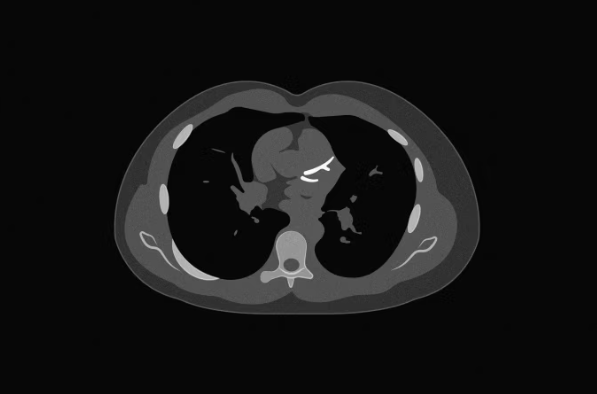

Bëhet fjalë për skanimin e kalciumit në arteriet koronare, i njohur si Coronary Artery Calcium scan, i cili mat nivelin e depozitave të kalciumit në arteriet e zemrës. Rezultatet e këtij testi variojnë nga 0 deri në 1,000 dhe po përdoren gjithnjë e më shumë nga mjekët për të përcaktuar rrezikun e pacientëve dhe nevojën për trajtim me ilaçe për kolesterolin.